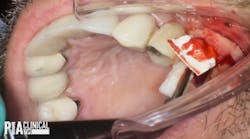

In this case, Dr. Scott Froum performs a live surgery on a 51-year-old male. The patient is in good health and taking no medications. He has an unrestorable tooth No. 13.

While there is an ample amount of soft tissue in the area, there is a buccal plate defect. According to the radiograph, tooth No. 13 was treated previously with a root canal (with an apicoectomy), and there is no periodontal ligament (PDL). This will be a difficult extraction.

Follow along and watch Dr. Froum perform this surgical procedure as he elevates the tooth, makes an osteotomy, performs osseous removal around the root, luxates the tooth, and removes the root. He then prepares to graft the socket by performing a soft-tissue envelope flap incision and placing the collagen material and a collagen membrane in order to preserve the ridge for subsequent dental implant placement.